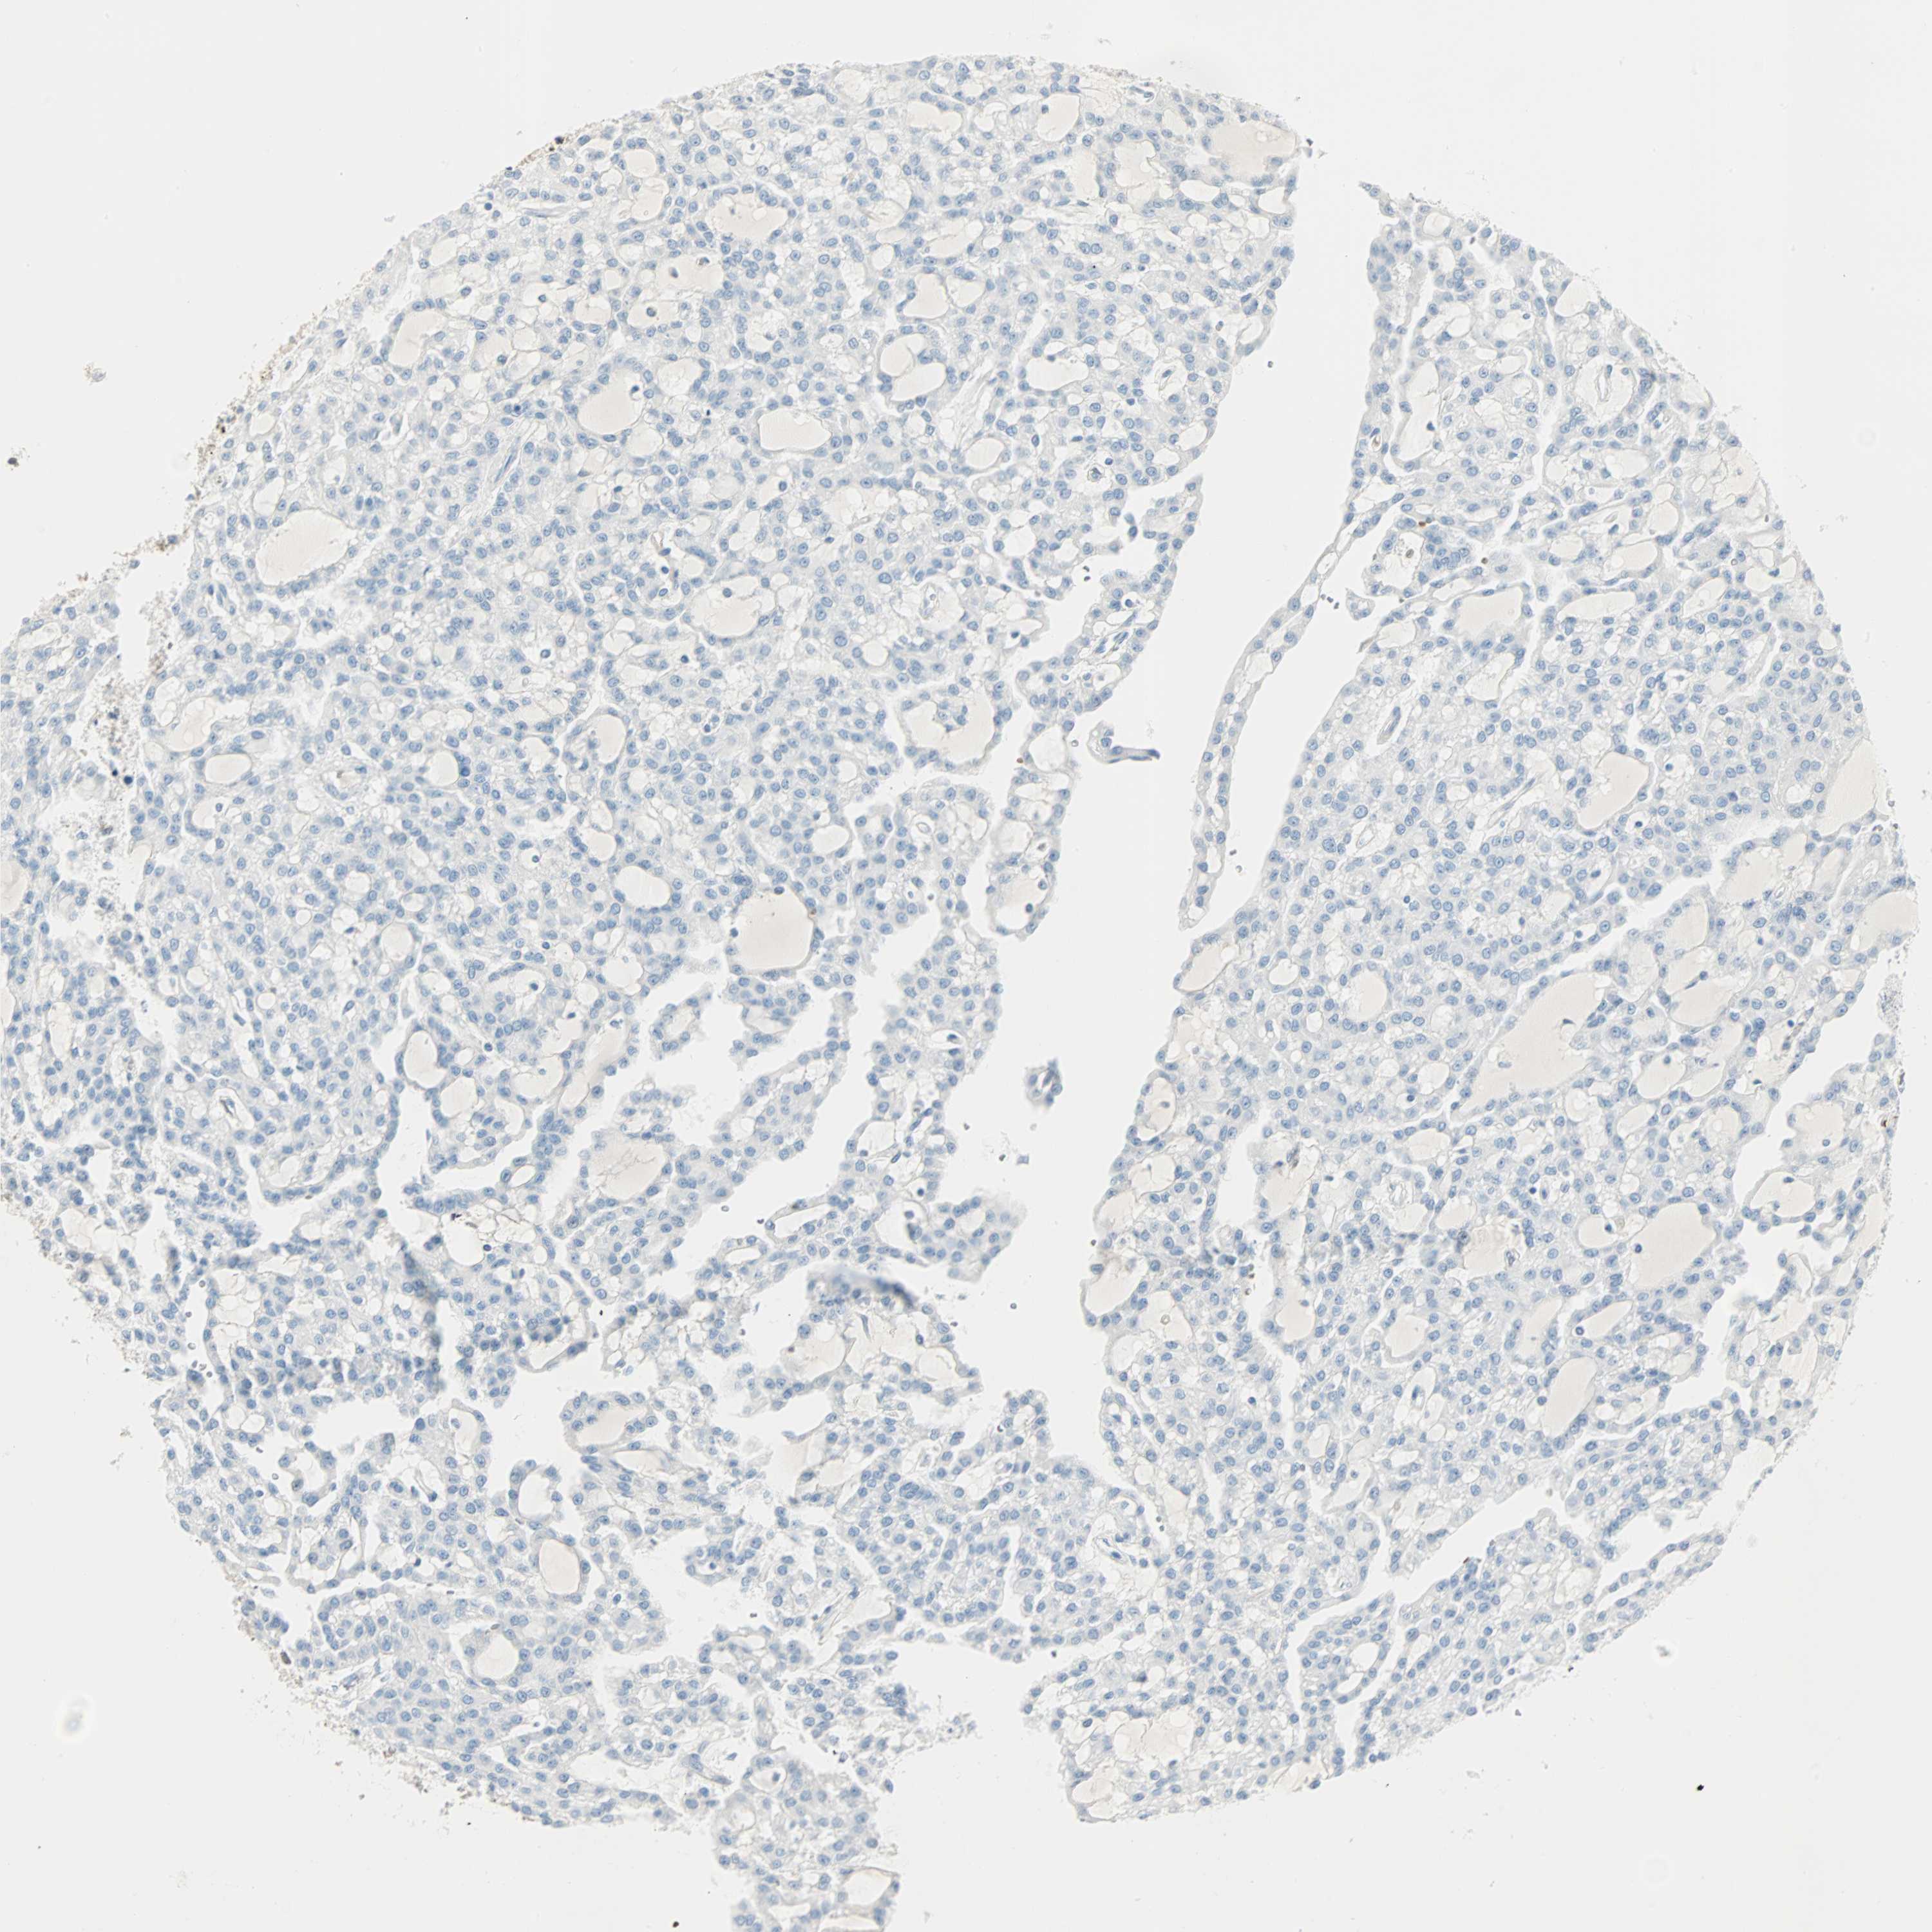

CANCER RENAL CANCER Show tissue menu

KICH TCGA KIRC TCGA KIRC VALIDATION KIRP TCGA PROTEIN RCC CPTAC PROTEIN EXPRESSION